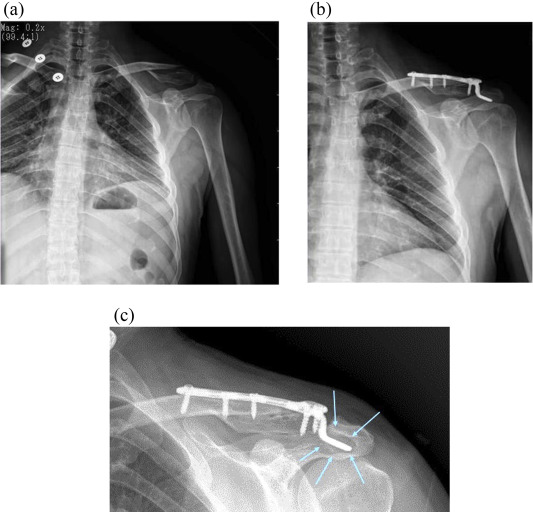

Fig. 1

Fig. 1.

(a) Anteroposterior radiograph of the right shoulder of a 33-year-old man who sustained a Neer type 2 distal clavicle fracture. (b) Early postoperative radiograph of the internal fixation using a hook plate with six holes. (c) Bony union was achieved after 12 weeks but the radiograph shows the subacromial osteolysis (blue arrows) around the tip of the hook of the same patient before implant removal (For interpretation of the references to colour in this figure legend, the reader is referred to the web version of this article).

There were no intraoperative complications. Radiographs showed union on the 3rd postoperative month in 13 patients, and on the 4th month in 3 patients. Three patients developed superficial skin infections after the operation, and they healed uneventfully with wound care. Radiological evaluation revealed a radiolucent area, located where the hook part touched the acromion, in 4 patients on the 3rd month, and in 6 patients on the 4th month. This was accepted as acromial osteolysis (Fig. 1 ). The plates were removed in all these 10 patients (62%) within the following month. One patient had a plate fracture on the 6th month (Fig. 2 ). During the plate removal, sufficient union was seen, therefore an additional procedure was not found to be necessary. Seven patients (42%) developed symptoms of subacromial impingement syndrome (SIS) after an average period of 2.5 months. Diagnosis was confirmed with a positive Neer test. Mean modified UCLA score at the final follow up was 32.75 (range 31–35). Twelve patients (68%) underwent plate removal due to acromial osteolysis, impingement syndrome and implant failure. After removal, the complaints regressed and shoulders' range of motion increased. At the final follow up; mean modified UCLA score was 32.75 (range 31–35). There were no acromioclavicular joint arthrosis in the patients (Table 1 ).